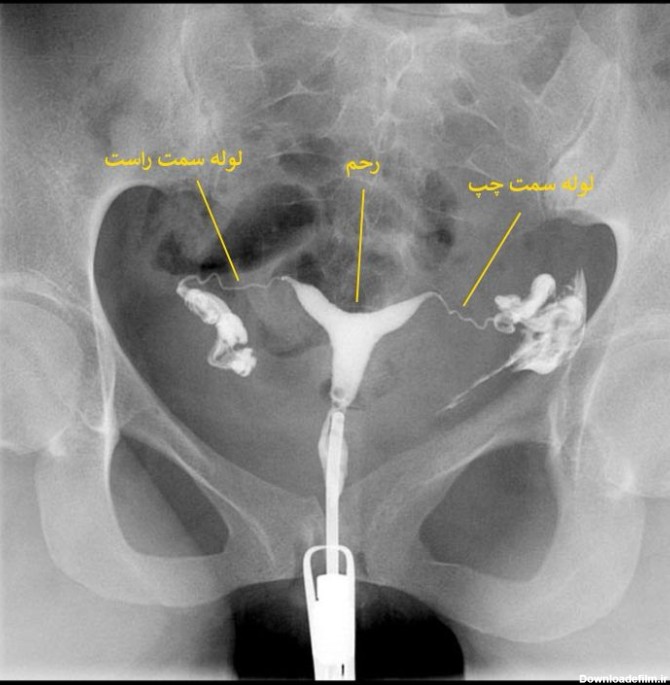

عکس رنگی رحم یا هیستروسالپنگوگرافی یک س.ن.گرافی تشخیصی برای ارزیابی ناهنجاریهای رحم است. دکتر مرتضی جورابیان سونوگرافی رنگی در اهواز انجام

عکس رنگی رحم یا هیستروسالپنگوگرافی نوعی روش تصویربرداری یا رادیوگرافی برای مشاهده رحم و لوله ها است که به وسیله نوعی اشعه ایکس به نام فلو